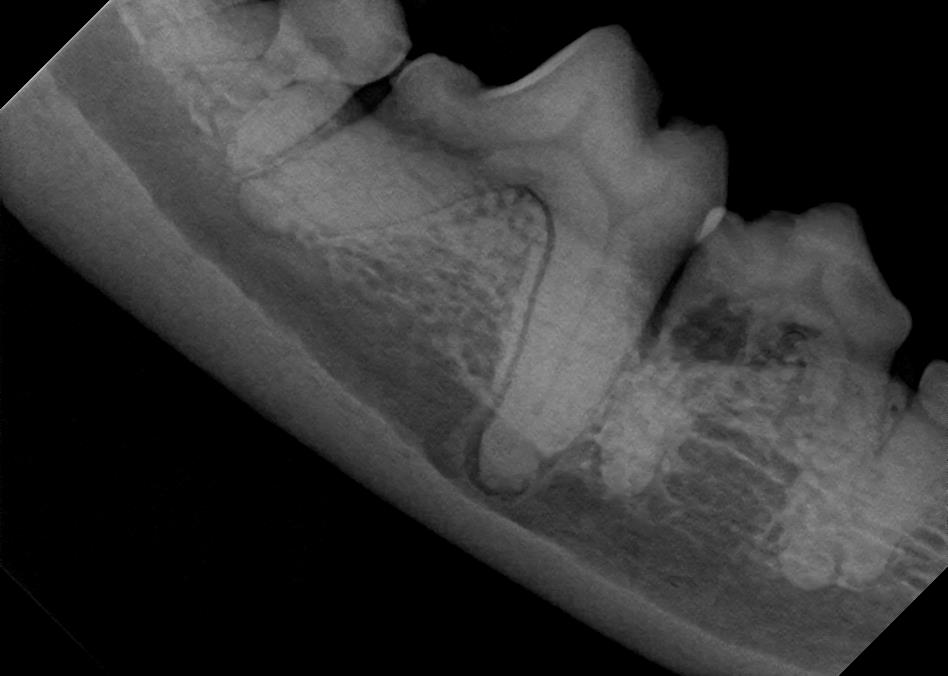

Examples of dental problems:

At A Couple of Vets, our animal hospital staff is well-versed in the latest dental cleaning techniques to remove plaque and tarter from the teeth’s surface as well as from below the gum line. We perform dental x-rays at every cleaning to ensure that the teeth are completely healthy. They may look good on the surface, but many problems occur below the gum line and are only visible with x-rays.